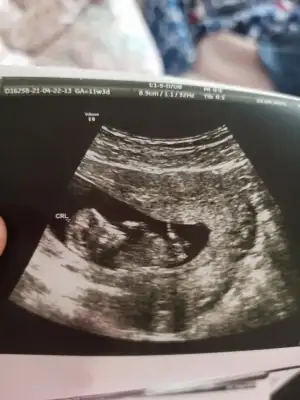

Teşekkür ederimKız görünüyor![]()

Tsk ederim mutlaka paylasicamEvet çok erkenşimdilik kız yönünde diyorum tekrar USG paylasin

Erkek görünüyor